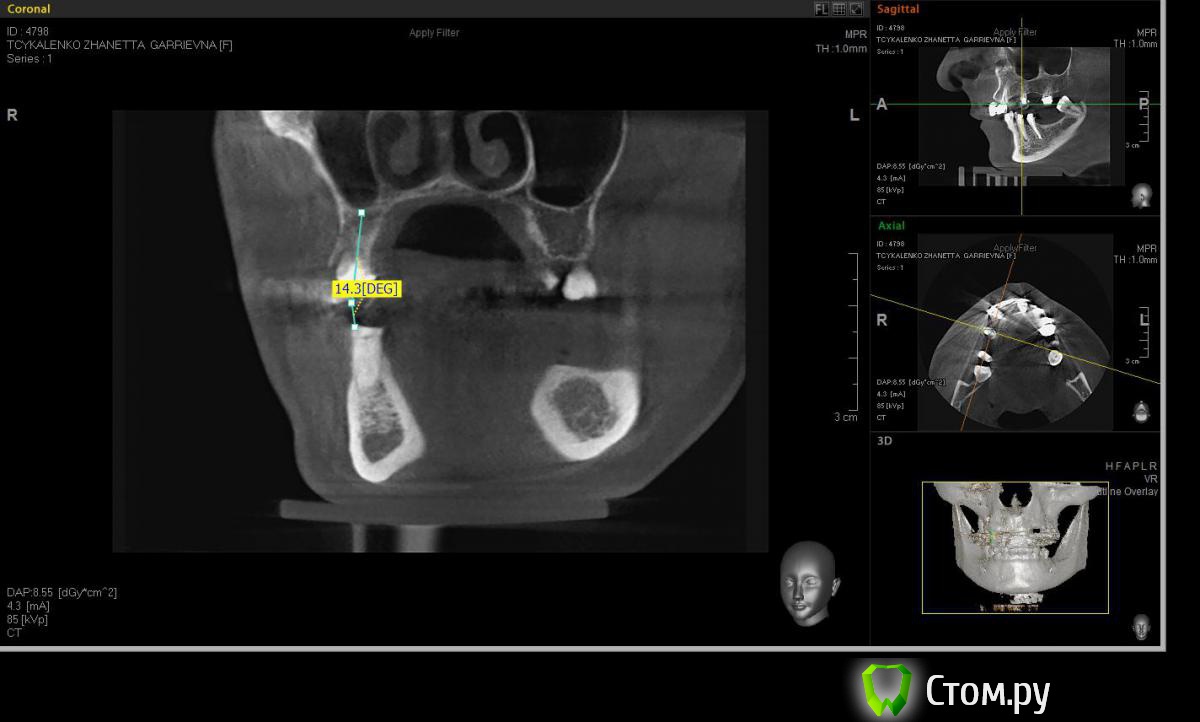

Евгений Ходыкин Опубликовано 20 мая, 2014 Автор Поделиться Опубликовано 20 мая, 2014 Ну как-то так. Сути не уловил) Свой зуб стоит совсем иначе, да и ширина гребня иная совсем... Ссылка на комментарий

АнтонТЛТ Опубликовано 20 мая, 2014 Поделиться Опубликовано 20 мая, 2014 Суть в том, что изначально не правильно угол замерили 1 Ссылка на комментарий

Евгений Ходыкин Опубликовано 20 мая, 2014 Автор Поделиться Опубликовано 20 мая, 2014 Суть в том, что изначально не правильно угол замерилиДак изначально я замерил строго по гребню, в условиях наибольшей ширины гребня, там угол под 30 и выходил. При ангуляции как у 1.5 у меня и получается дефицит кости, что примерно изобразил на схеме постановки имплантата. Поправьте, если не прав... Ссылка на комментарий